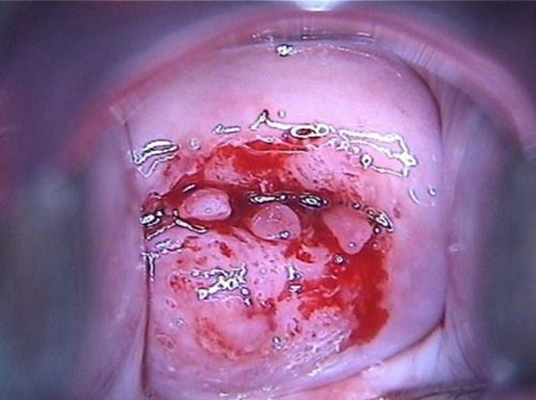

子宮頸炎圖片

宮頸炎